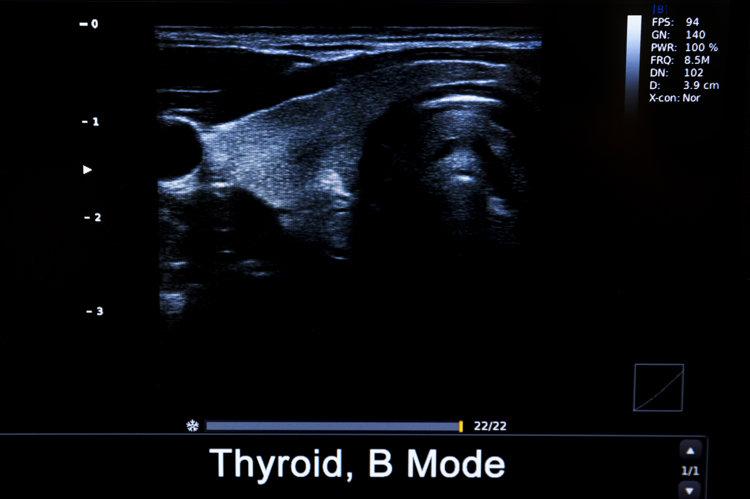

• 甲狀腺結節

甲狀腺結節是指甲狀腺組織內出現的侷限性腫塊,會隨着吞嚥動作上下移動。

中國醫學科學院腫瘤醫院山西醫院頭頸外科主任李德志表示,B超檢查中有20~30%的人會檢出大小不一的甲狀腺結節,大部分爲良性,最終診斷爲惡性的概率僅有3~4%。但還是建議普通人每年進行一次甲狀腺檢查。